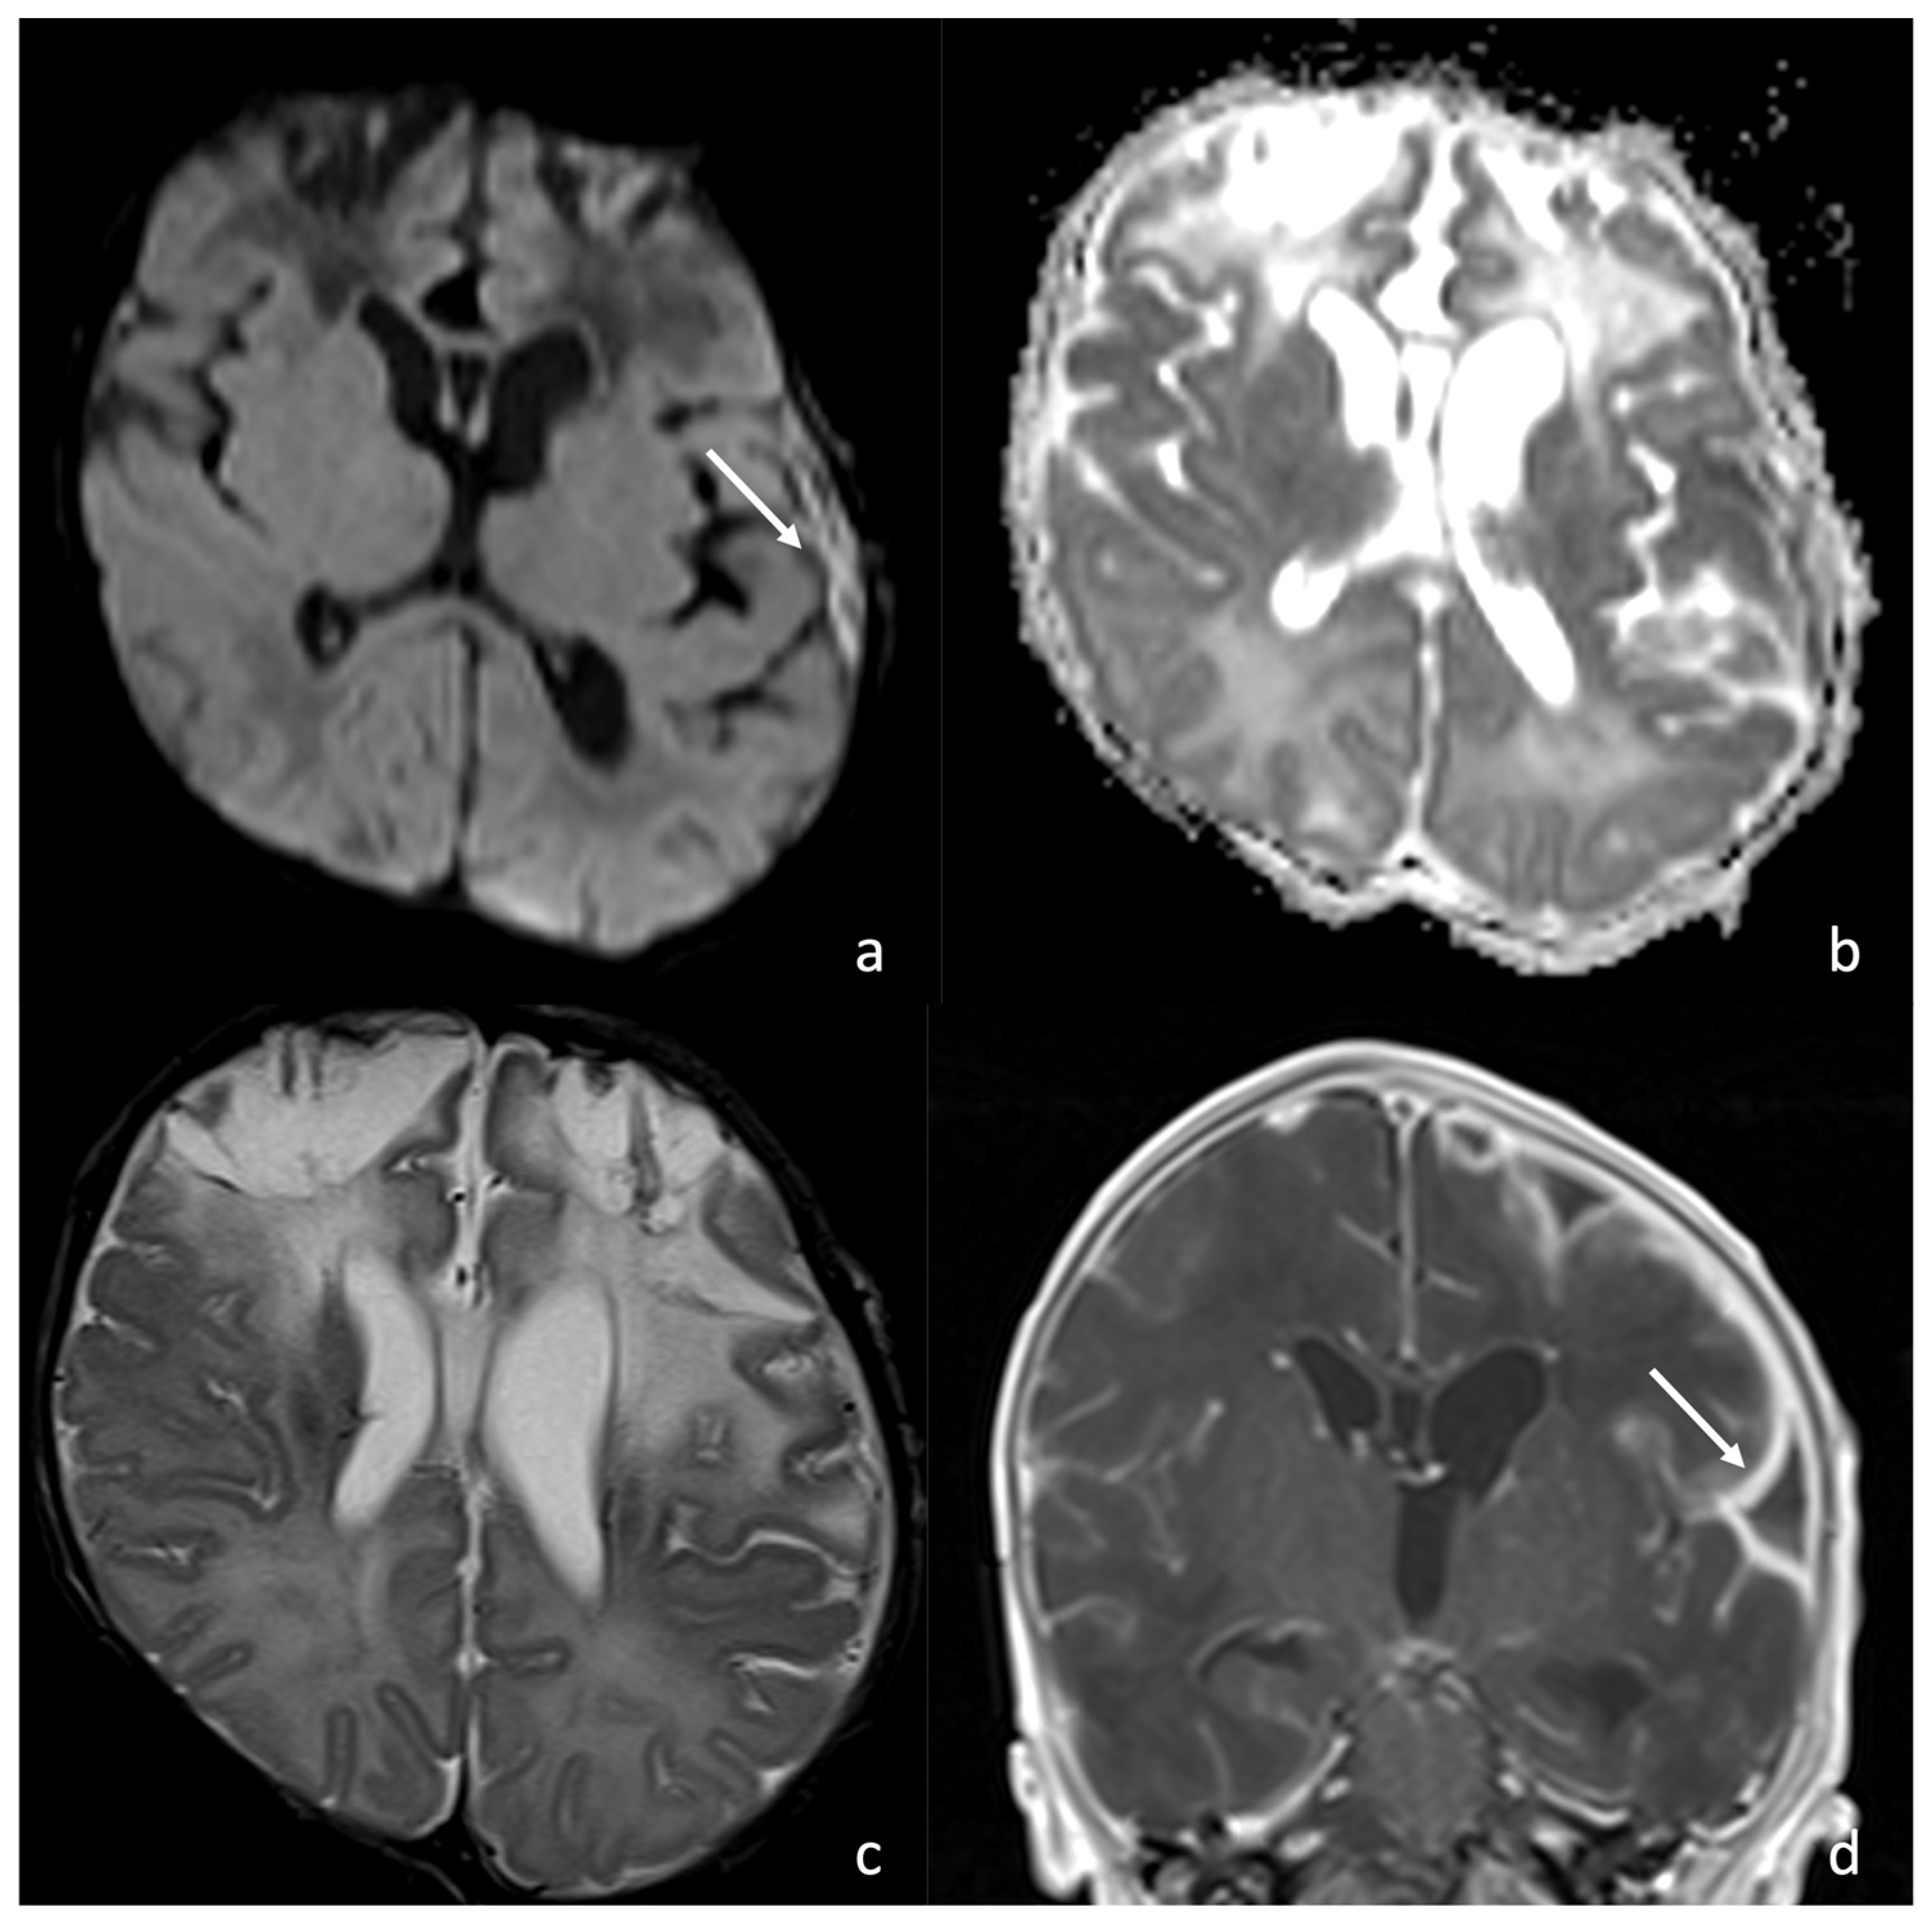

6. Meningoencephalitis Stage: Neuroradiological Findings

6.2. Infarcts